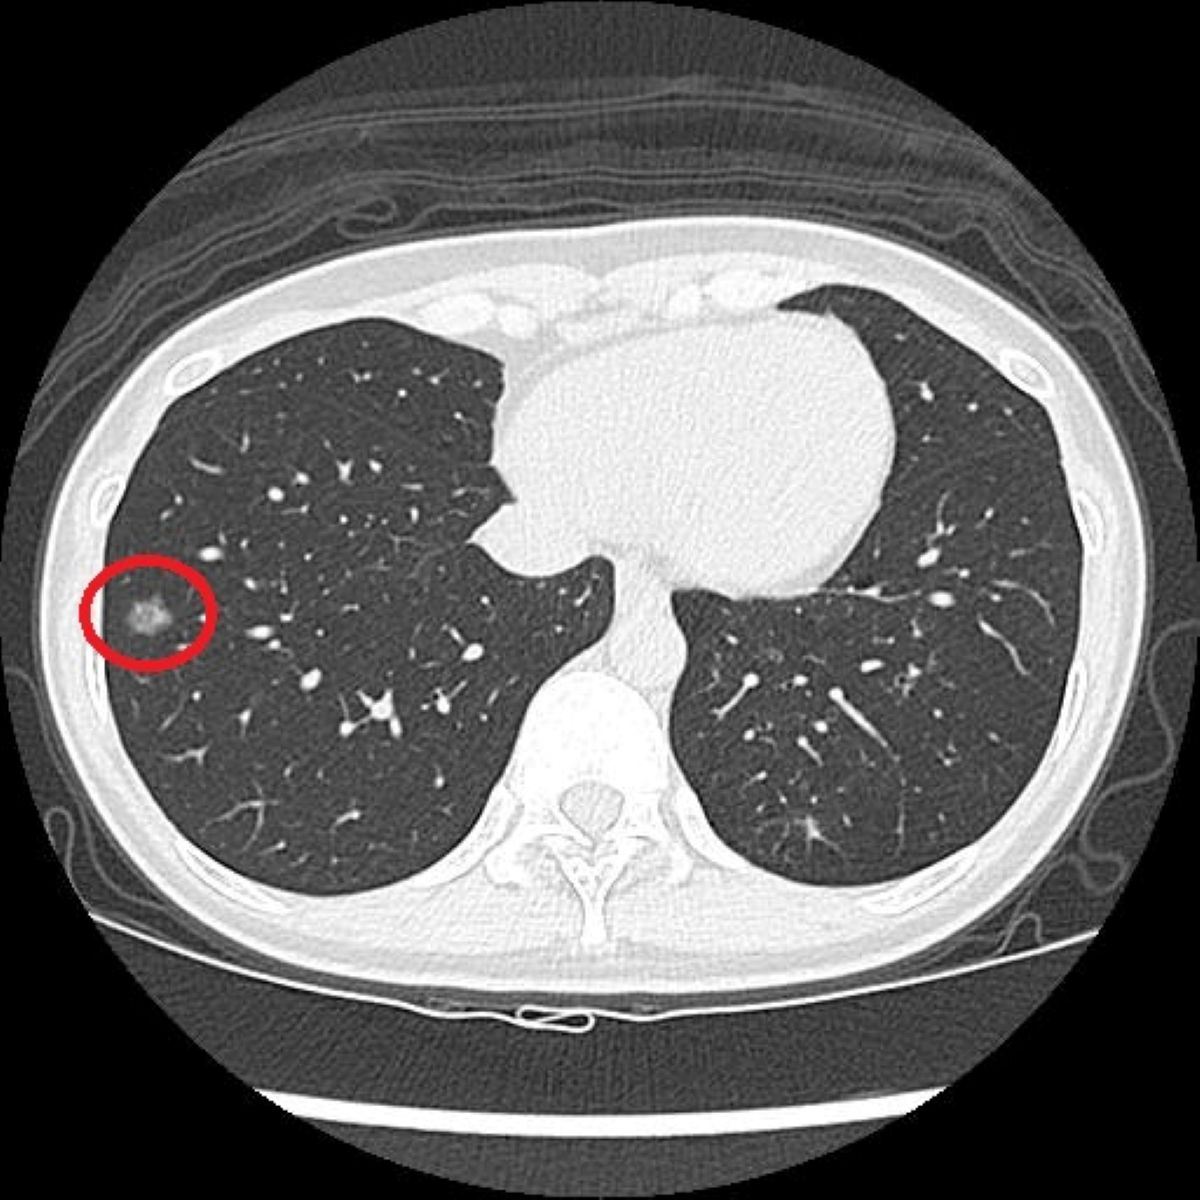

41歲陳小姐過去有長期的吸菸史,在醫療團隊的協助下戒菸近2年,雖沒有任何不適,但仍定期留意自身健康。因符合政府公費「低劑量電腦斷層(LDCT)」篩檢條件,她依建議至醫院接受檢查,卻意外發現右肺有一顆約1.2公分的毛玻璃結節,被轉診至胸腔外科門診,由醫師進行單孔胸腔鏡微創手術切除病灶,術後病理檢查確診為肺腺癌第一期,目前定期回診追蹤中。

篩檢方面,洪嘉聰指出過去是以胸部X光作為工具,但由於影像為2D平面,對於體積小或位置較隱蔽的病灶辨識能力有限;若是改以一般劑量的電腦斷層檢查,雖能提升解析度,但其輻射劑量相對較高,且需較長時間代謝,不適合作為常規或大規模篩檢工具。而LDCT篩檢則是利用比傳統電腦斷層更低的輻射劑量,從多個角度掃描胸腔,重建出清晰的橫切面和立體影像,有助於偵測肺部的微小結節。相較於傳統胸部X光只有少數約7%的受檢者會出現疑似異常影像,LDCT能使初次篩檢的陽性比例提升至約23%~24%,大幅增加早期病灶被發現的機會。